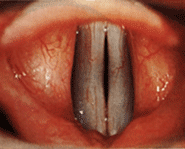

“They are two muscles which come together over your windpipe like this,” he said indicating the gagging hole on the screen that was my throat.

He showed me that my right chord was not working correctly and was not moving sufficiently to close the space over my windpipe.

If you would like to see vocal chords being tested like mine were here is the identical examination performed on a young American soprano. Don’t be squeamish, it is really interesting: